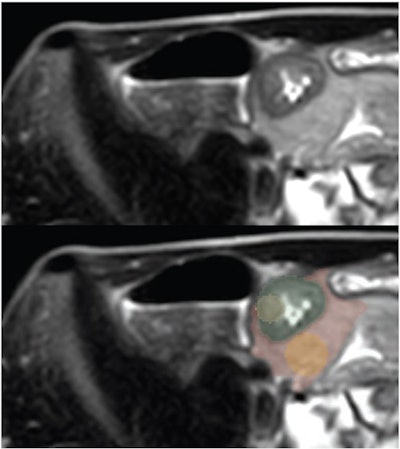

17-year-old patient with Crohn disease. Axial T2-weighted SSFSE images show greatest terminal thickness -- without (top) and with (bottom) four ROI segmentations. (Green = whole-bowel ROI; yellow = bowel-core ROI; red = whole-fat ROI; orange = fat-core ROI.) Image and caption courtesy of the American Journal of Roentgenology.Three pediatric abdominal radiologists flagged the presence of ileal Crohn's disease on these SSFSE images. The study's reference standard was the clinical diagnosis of ileal Crohn's disease following positive endoscopy and biopsy, the group explained.